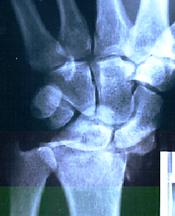

A few years after starting on the cellular nutrition products I had a nasty accident. I broke a wrist very badly. The radius was shattered.

The surgeons said there were at least 50 points of break and that there was absolutely no chance of blood circulation returning to the bone. They said that they would just lock it all together and make it rigid but there was nothing to join it onto. They cut the wrist open, took out the bone pieces and cleaned it up.

Then they took the large pieces and reconstructed the bone. They put a pin in between each tendon and a lateral pin to stabilize. The small pieces of bone chips were put into the cracks to try and graft the pieces together.

6 weeks later, when the time came to take the cast off, the surgeons were stunned by the X-rays. They showed no area where the circulation had not returned. They redid all the tests when they took the pins out in the 4th month. Again they found that the circulation had completely returned.